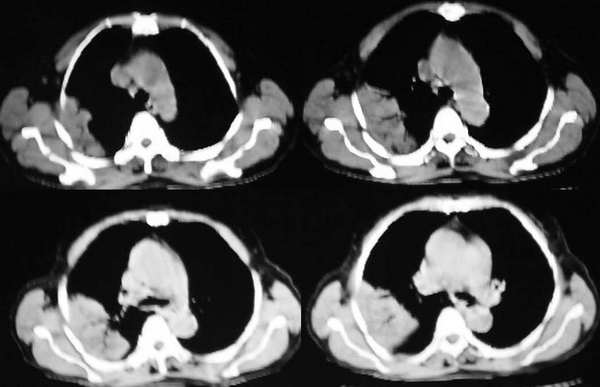

右上叶后段见大片状实变阴影,见含气支气管征,近肺门见支气管血管束增粗,上腔静脉后见小淋巴结. 后胸膜腔见少量积液. 印象:1,大叶性肺炎.2,节段性肺炎<混合菌感染>.3.建议抗炎后复查待除外其他病变

首先考虑炎症:团块软组织阴影,内有支气管充气征。

其次肺淋巴瘤也可以为肺外围的肿块,其内见支气管充气征。

右肺实变影,内见空气支气管征,纵隔内未见异常结构,肺炎